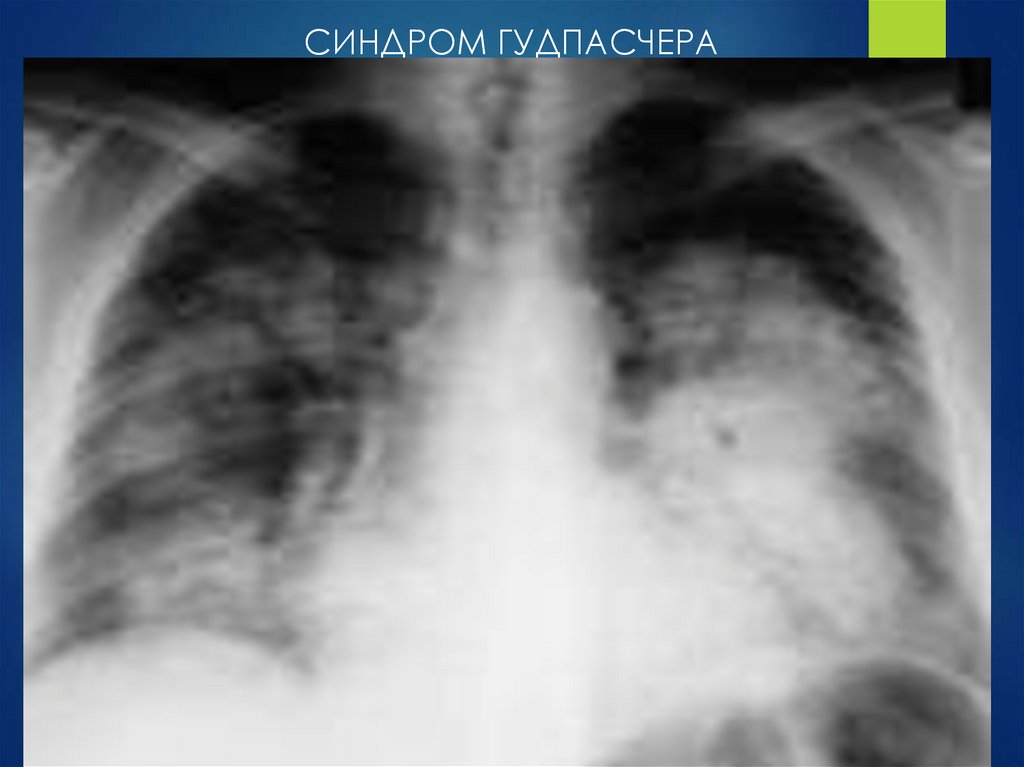

СИНДРОМ ГУДПАСЧЕРА